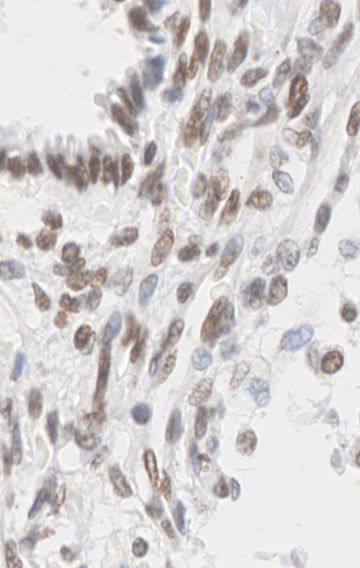

3.5.2 Data

The data presented in this study have been acquired from digital images of immunohistochemistry stainings that were performed on archival tissue obtained from the neurobiobank of the Division of Neuropathology and Neurochemistry at the Medical University of Vienna. Stainings have been performed according to standard procedures (citep \@BBN(Guo et al., 2024; Schwaiger et al., 2023)). Figure 11 (a)-(c) shows a tumour biopsy of a gliosarcoma patient stained for the astrocyte marker GFAP (brown signal, cytoplasmic localization) and counterstained with Hematoxylin (blue signal, nuclear localization). Figure 3 (d)-(e) shows fetal cerebellar tissue stained for the epigenetic mark H3K27me3 (brown signal, nuclear localization) and counterstained with Hematoxylin (blue signal, nuclear localization). The stained sections have been digitalized on a NanoZoomer 2.0-HT digital slide scanner C9600 (Hamamatsu Photonics, Hamamatsu, Japan). The corresponding software NPD.Viewer2 was used to export the scanned images to tiff files. Here, we performed individual scans of a selected imaging area with different numbers of focus points. We chose either 1, 3 or 9 focus points while not changing the spatial settings for the selected field of interest. The image with 9 focus points, allowing the highest resolution, serves as the reference image.

Refer to caption

(b) (18.6, 0.80, 0.10)

(c) (23.6, 0.91, 0.33)

(d) Reference

(e) (22.9, 0.81, 0.11)

(f) (27.0, 0.87, 0.22)

Figure 11: Data acquired with a slide scanner and 9 (a)(d), 3 (b)(e) and 1 (c)(f) focus points. The image with 999 focus points serves as a reference here. PSNR and SSIM misjudge the tiny spatial misalignment and therefore favor the blurry images with 1 focus point. LPIPS is able to ignore these spatial misalignments.

FR-IQA mismatches

Although the spatial settings for the selected scan area of interest were not changed during the experiment, the physical performance of the scanner showed slight spatial deviations of the selected area between individual scans and thus does not allow for high spatial accuracy during re-scanning processes. PSNR and SSIM fail to correctly assess the images in Figure 11 as they are very sensitive to that kind of misalignments. Whereas clearly the scan with 3 focus points corresponds much better to the reference as the blurred scan with 1 focus point, see (b) and (e) versus (c) and (f), both measures incorrectly judge the blurred scan as better. This wrong judgement due to a tiny spatial change is very problematic in the respective framework, as it is impossible to guarantee completely exact spatial alignment, even if no other settings had been changed during the scanning process. LPIPS is able to correctly judge the rank of quality here.